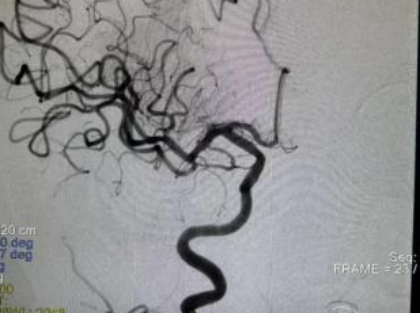

术前造影图

右侧大脑中动脉M1段闭塞